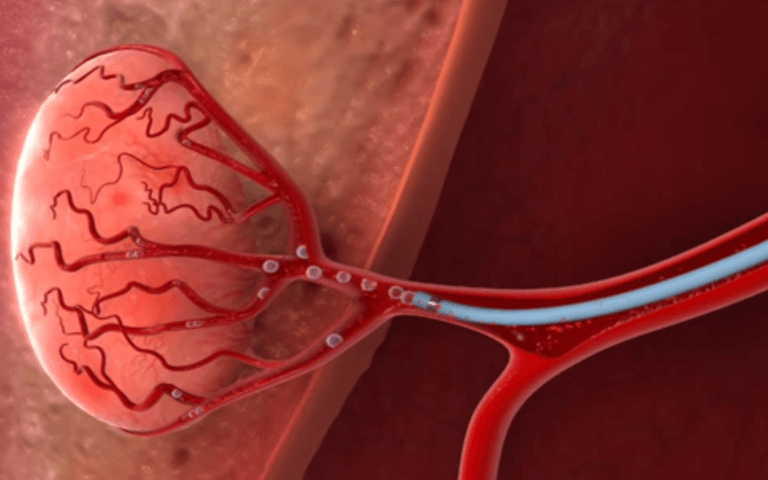

Embolização de mioma uterino

Embolização prostática